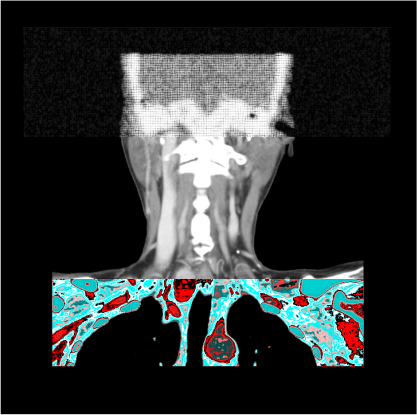

- Axial, coronal and sagittal images in soft-tissue window (WW: 400, WL:40), without exceeding 3mm slice thickness.